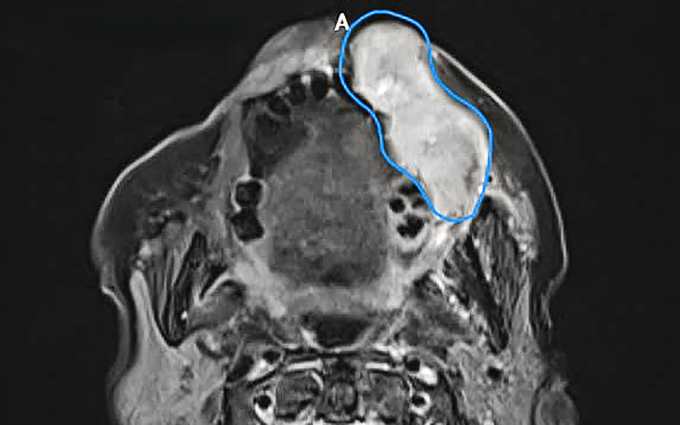

Ảnh CT ghi nhận khối u ác tính (vùng màu xanh) từ niêm mạc miệng xâm lấn ra má, môi người bệnh. Ảnh: Bệnh viện Đa khoa Tâm Anh

Bà Tình, 80 tuổi, xuất hiện khối u 6 tháng trước rồi tăng dần kích thước khiến mặt bên trái sưng căng đẩy vùng má, môi lồi lõm, lệch hẳn ra ngoài, phía trong miệng lở, rỉ dịch. U lớn nhanh gây đau khiến bà không nói rõ, không thể ăn uống, sụt 5 kg. Kết quả sinh thiết tại Bệnh viện Đa khoa Tâm Anh TP HCM cho thấy khối u dài 7 cm dày 4 cm là ung thư niêm mạc má giai đoạn ba.